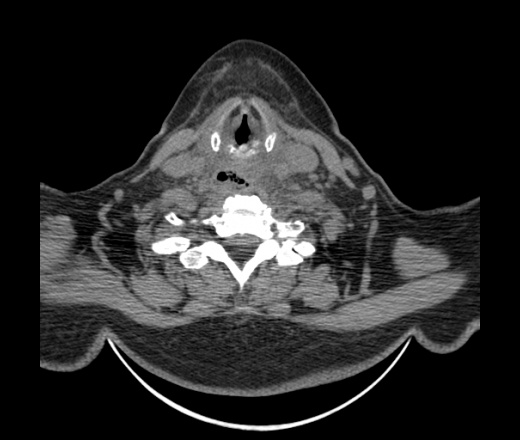

Женщина поступила в х/о спустя 4 дня после того как при употреблении карася подавилась костью.

Наличие газа в средостении на протяжении тел С2-С6 (медиастинальна эмфизема); рыбная кость на уровне тела С6.

При всем уважении, но говорить о медиастинальной эмфиземе, оценивая мягкие ткани шеи, как-то слишком резко. На мой взгляд, это ретрофарингеальное пространство.

Эвакуировали почти 100мл гноя. Но кость не смогли найти. Думаю что она даст дальнейшее ослоднение. Эндоскопически за черпалонадгортаной звязкой не смогли зайти в пищевод, все мягкие ткани отечные, просвет пищевода сдавлен. По всей видимости параэзофагеальная клетчака тоже задействована. Эмпиема, если ее можно так назвать, незнаю как правильно дошла до уровня яремной вырезки. Чем закончиться напишу. Ждем медиастинита.

Согласен с Вами; конечно, наличие газа в клетчатке ретрофарингеального пространства (затмение с опечаткой..). К сожалению, процесс "продвигается" к медиастиниту. Но почему никто, не отмечает наличие рыб. кости; или это для Всех очевидно?

Кость то мы сразу выявили, размеры где то 17*2мм, но ее так и не получается найти в этой каше